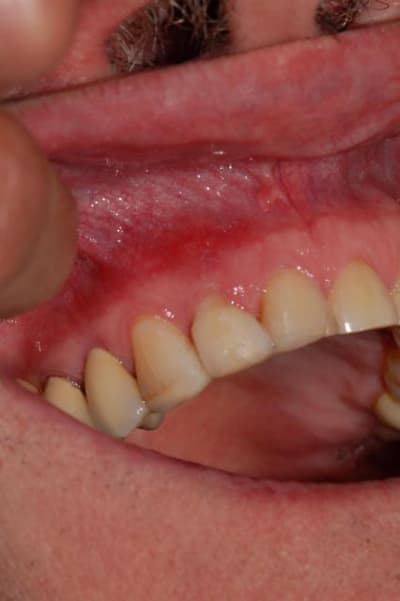

cas d'un patient arrivé vendredi en urgence, volumineux abcès vestibulaire sans fistulisation, au sondage poche de 8 mm en proximal: mésiale et distale, gencive attachée en vestibulaire,mobilité 3 pas le temps de prendre des photos, mais simplement une radio.

Traitement: assainissement par débridement des poches et de l'abcès à la povidone iodée diluée, puis au calbénium dilué, aéropolissage de la zone au bicarbonate puis injection dans les poches et dans la fistule crée au laser diode fibre 300µ, d'eau oxygénée à 10 volumes, attente 5 minutes puis activation au laser diode fibre 400µ et enfin biostimulation au laser diode fibre défocalisante pendant 1 mn. J'ai solidarisé 12 à 11 et 13, au composite flow.

j'ai oublié de vous dire que la dent n'est plus du tout mobile et que la gencive n'a plus d'aspect inflammatoire.